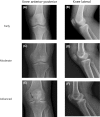

Figure a, b show early stage of hemophilic arthropathy in knee joint: AP and lateral view. Note no osteoporosis, no enlarged epiphysis, no irregular subchondral surface, no narrowing of joint space, no subchondral cyst formation, no joint margin erosion, no gross incongruence of articulating bone ends and no joint deformity; Figure c, d show moderate stage of hemophilic arthropathy in knee joint: AP and lateral view. Note the osteoporosis, no enlarged epiphysis, no irregular subchondral surface, narrowing of joint space (>1 mm), no subchondral cyst formation, no joint margin erosion, no gross incongruence of articulating bone ends and no joint deformity. This is Petterson grade 2; Figure e, f show advanced stage of hemophilic arthropathy in knee joint: AP and lateral view. Note the osteoporosis, no enlarged epiphysis, partially irregular subchondral surface, narrowing of joint space (<1 mm), 1 subchondral cyst formation (black arrow, e), no joint margin erosion, slight gross incongruence of articulating bone ends and no joint deformity. This is Petterson grade 6

Figure a, b show early stage of hemophilic arthropathy in ankle joint: AP and lateral view. Note no osteoporosis, no enlarged epiphysis, no irregular subchondral surface, no narrowing of joint space, no subchondral cyst formation, no joint margin erosion, no gross incongruence of articulating bone ends and no joint deformity; Figure c, d show moderate stage of hemophilic arthropathy in ankle joint: AP and lateral view. Note the osteoporosis, no enlarged epiphysis, no irregular subchondral surface, narrowing of joint space (>1 mm), no subchondral cyst formation, no joint margin erosion, no gross incongruence of articulating bone ends and no joint deformity. This is Petterson grade 2; Figure e, f show advanced stage of hemophilic arthropathy in ankle joint: AP and lateral view. Note the osteoporosis, no enlarged epiphysis, partially irregular subchondral surface, narrowing of joint space (<1 mm), 2 subchondral cyst formation (black arrow, e), joint margin erosion (black arrow, f), gross incongruence of articulating bone ends and no joint deformity. This is Petterson grade 7